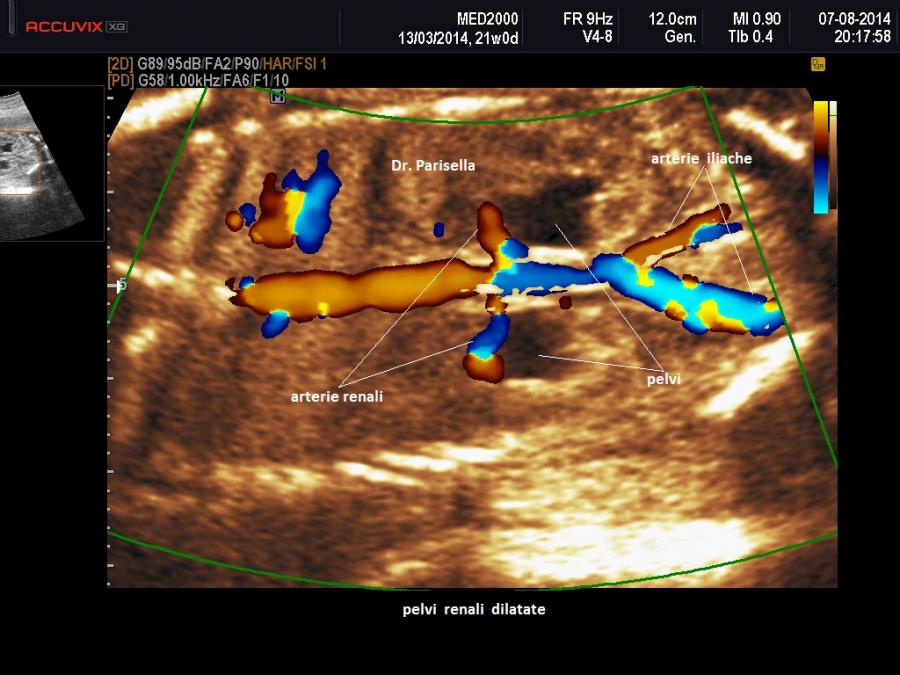

• megauretere: si presenta come una struttura tubulare a decorso rettilineo o tortuoso tra pelvi renale e vescica; il color doppler può aiutare a distinguerlo da strutture vascolari e la continuità con la pelvi renale spesso dilatata lo distinguono dalle anse intestinali. Spesso il megauretere è un segno tardivo per cui il riconoscimento definitivo avviene nel terzo trimestre o alla nascita.

• pielectasia e calicectasia: consiste nella dilatazione della pelvi o bacinetto e dei calici; la diagnosi di pielectasia è effettuata allorquando il diametro antero-posteriore della pelvi è superiore ai 7 mm. Nelle forme severe di pielo-calicectasia si ha compressione del parenchima renale con successiva corticalizzazione.